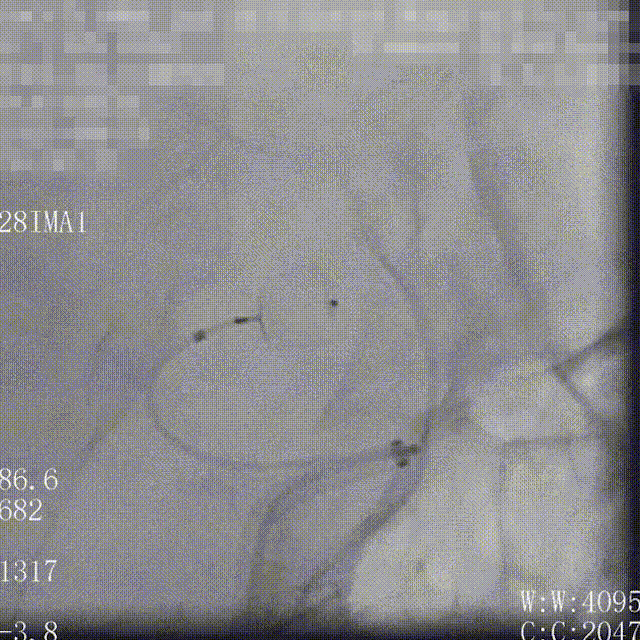

WEB™经由VIA™微导管送入动脉瘤瘤腔并完全释放。术后即刻造影显示WEB™尺寸合适,贴壁良好,分支等血流通畅。解脱后再次造影,可见动脉瘤瘤腔内有明显造影剂滞留。

术后3个月随访,WEB™完全栓塞,动脉瘤完全闭塞。